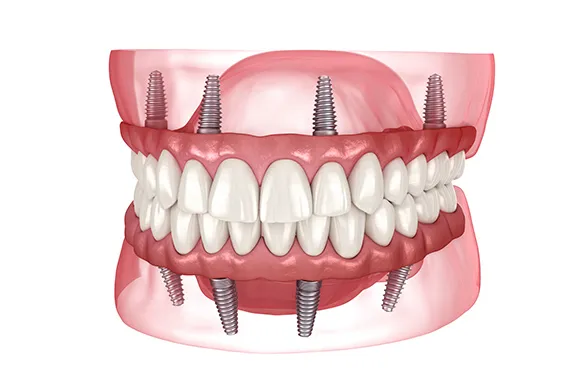

オールオンフォー

オールオンフォー(ALL ON 4)とは、総入れ歯の方や歯を多く失ってしまった場合に、インプラントを4本バランスよく埋入する手術のことです。従来の治療方法だと、失ってしまった歯の本数分のインプラントを埋入する必要があり、手術時間が長くかかり負担が大きく費用も高くなりますが、オールオンフォーは必要最小本数の4本のみのインプラントなので、患者さまの負担が軽いです。